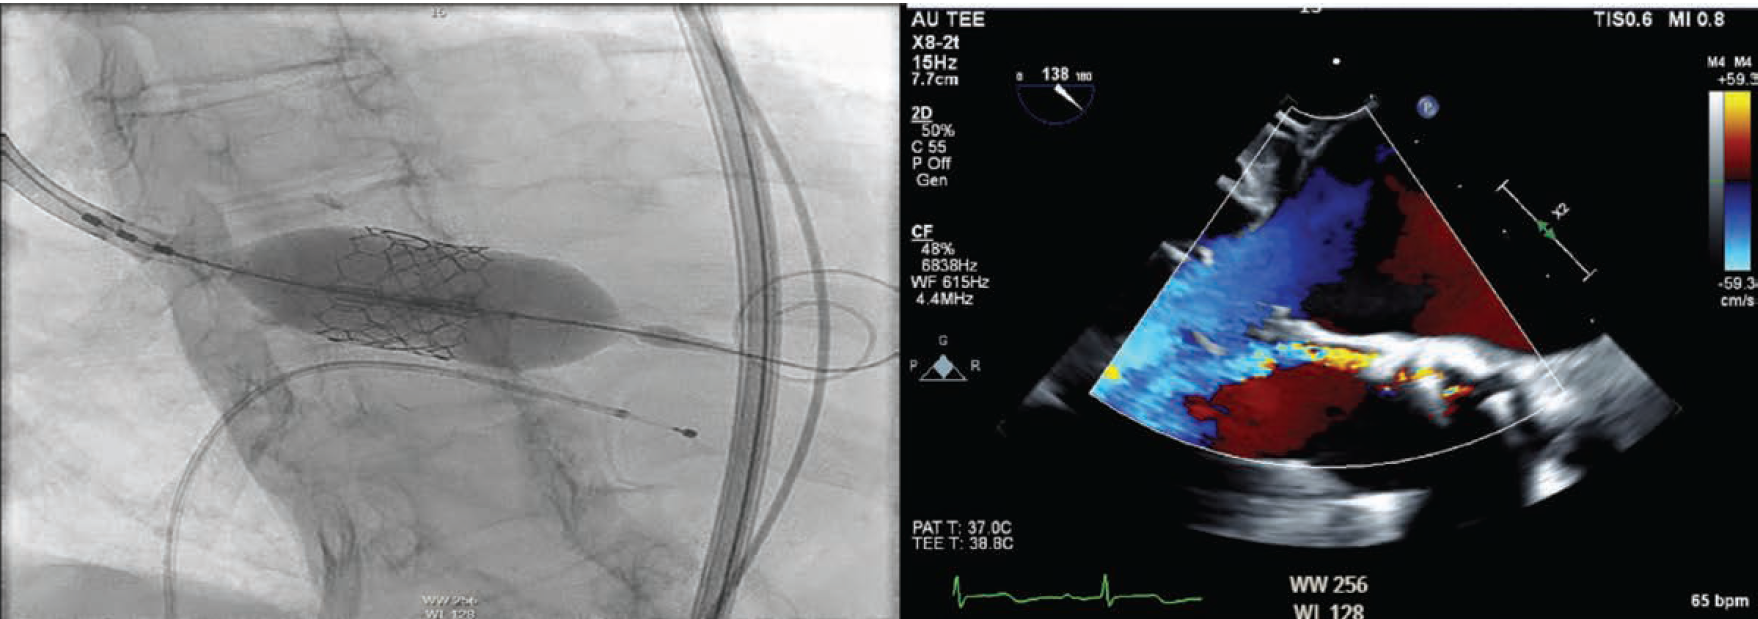

After a brief period of medical optimization, the patient underwent TAVR with a 23 mm Edwards Sapien 3 Ultra Resilia valve and cautious post dilation with nominal balloon preparation (Figure 2A). Post TAVR, her ejection fraction improved to 35%-40%, with a mean gradient of 11 mmHg and mild to moderate paravalvular leak (PVL). The patient was discharged the following day with a plan for close follow-up.

A 7 French (Fr), 45 cm sheath was inserted via the right femoral artery. The PVL was crossed with a 7 Fr multipurpose guide catheter, a Berenstein catheter in a mother-daughter technique, and a Minamo coronary wire (Asahi Intecc). The Berenstein catheter was then advanced into the left ventricle and confirmed with fluoroscopy to be completely outside the valve frame (Figure 3). A Confida wire (Medtronic) was placed in the left ventricular apex, after which the Berenstein catheter was removed. A 7 Fr Railway sheathless access system (Cordis) was utilized to assist the multipurpose guide in crossing into the left ventricle, followed by deployment of an 8 mm Amplatzer Vascular Plug II (Abbott). This was selected to ensure coverage of the two jets on either side of the calcific annular nodule with the proximal and distal disks. The plug was successfully deployed reducing the PVL to trace. Intraoperative TEE showed trace PVL (Figure 4).